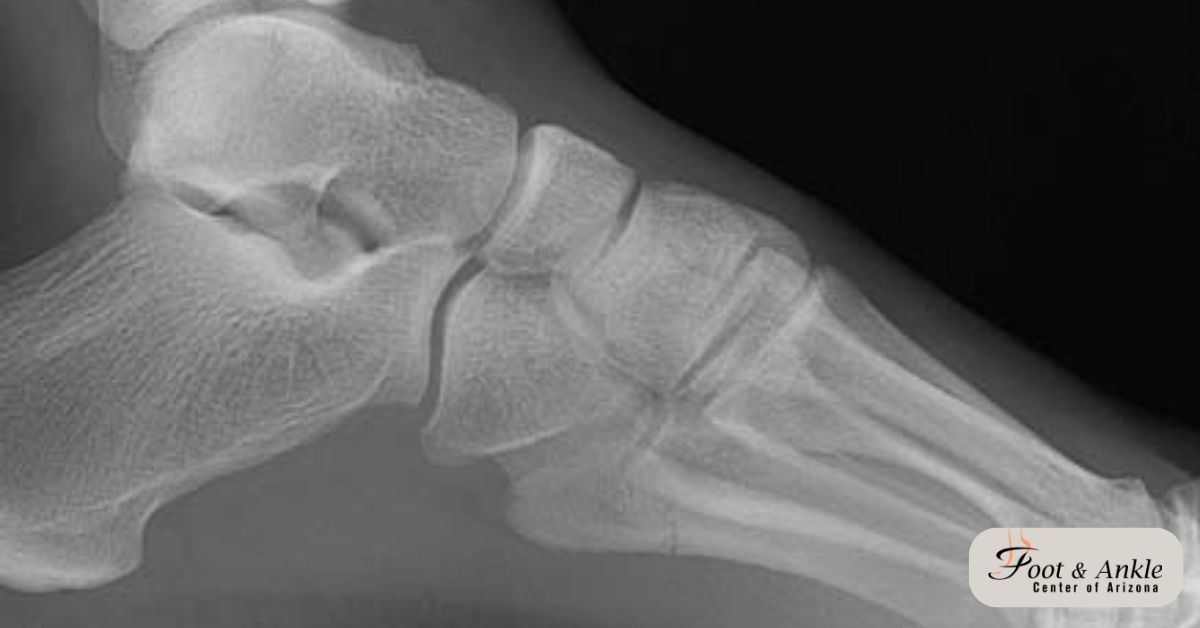

Diagnosis of a 5th Metatarsal Fracture

If you suspect that you have a fractured 5th metatarsal, you should see a podiatrist (foot and ankle specialist) at the Foot and Ankle Center of Arizona. Our doctor will examine your foot for pain, swelling, and tenderness. Imaging studies may be needed to confirm the fracture and the location and extent.

X-rays: X-rays are used both in diagnosis and for monitoring your healing. These will also be billed at a separate CPT code.